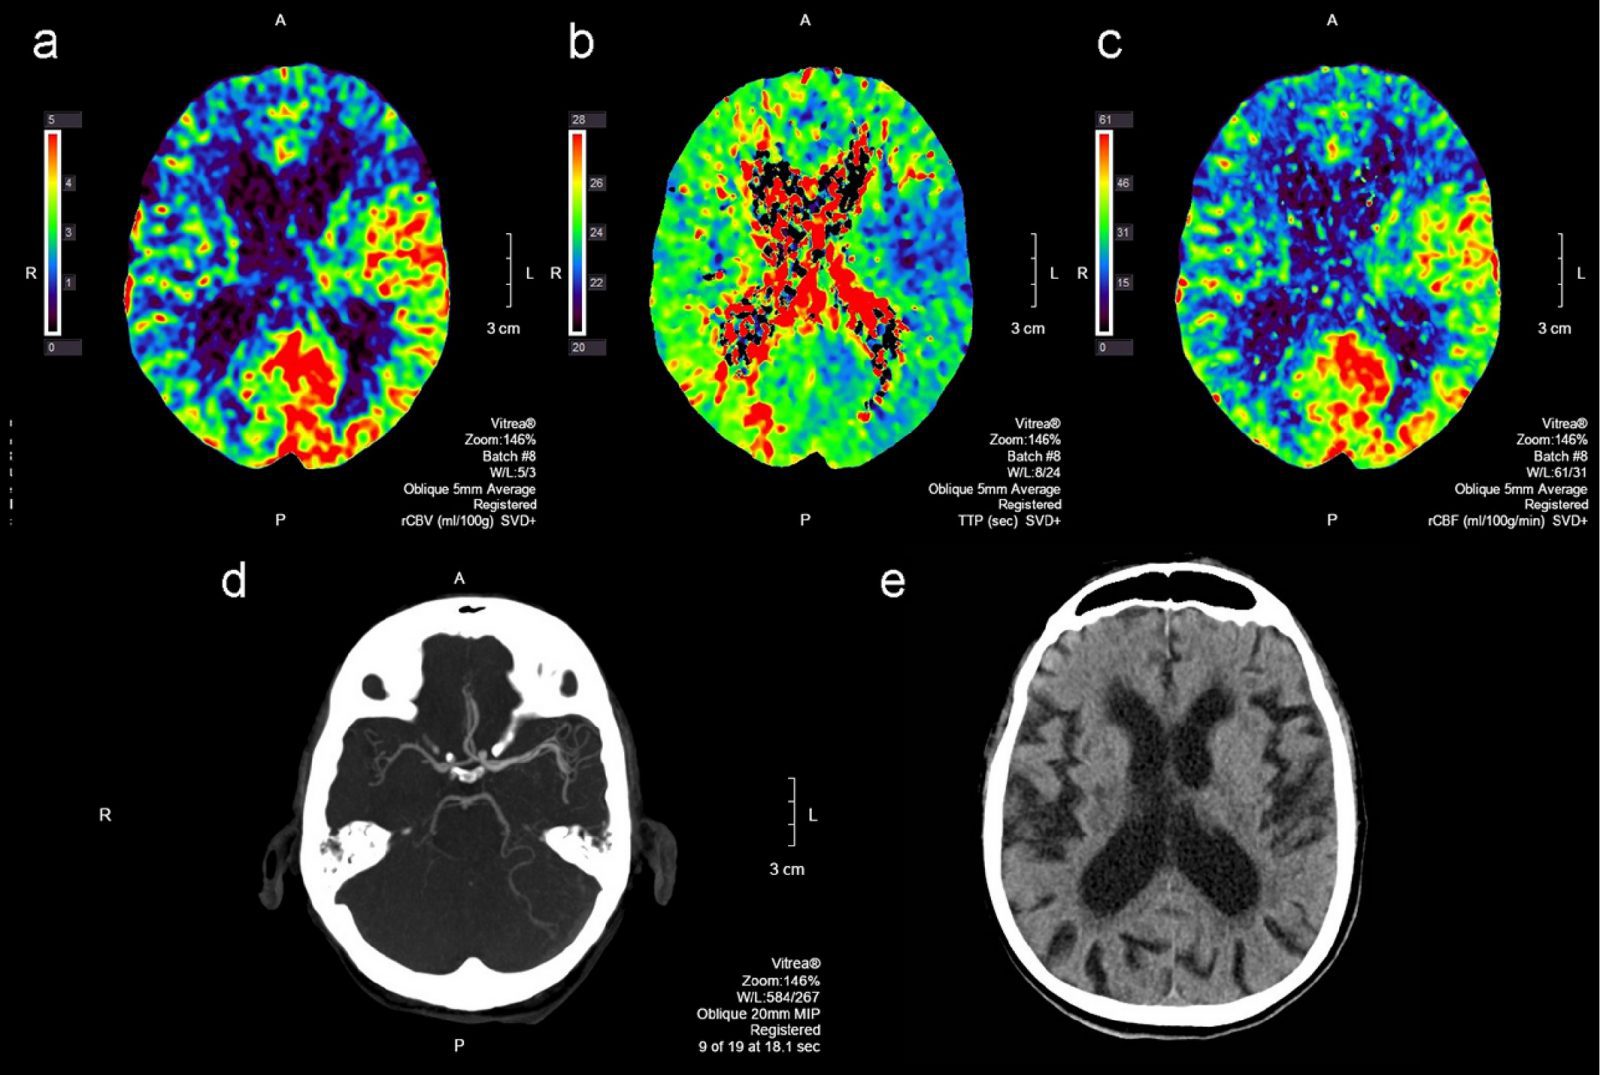

تصویربرداری پرفیوژن

تصویربرداری پرفیوژن پرفیوژن یک عملکرد بیولوژیکی اساسی است که به انتقال اکسیژن و مواد مغذی به بافت از طریق جریان خون اشاره دارد. تصویربرداری پرفیوژن به ریز عروق حساس است و در طیف گسترده ای از کاربردهای بالینی ، از جمله طبقه بندی تومورها ، شناسایی مناطق سکته مغزی ، و توصیف سایر بیماری ها اعمال شده است. تکنیک های تصویربرداری پرفیوژن با استفاده از ماده حاجب برون زا طبقه بندی می شوند. روش های بولوس ، با تزریق ماده

آنالیز پرفیوژن

محاسبه آنالیز پرفیوژن بر اساس اندازه گیری هایی است که هنگام حرکت بولوس در سیستم خون انجام می شود. نقطه شروع عملکرد ورودی شریانی (AIF) است که قبل از حرکت بولوس عامل کنتراست از میان منطقه مورد نظر (ROI) در شریان اندازه گیری می شود. آنالیز پرفیوژن با استفاده از مدل کینتیک نیاز به ارزیابی پارامتر های تبادل ماده کنتراست زا بین خون و بافت را دارد. برای ساده سازی پارامترهای آنالیز پرفیوژن ، یک رویکرد آنالیز بصری حاوی روش